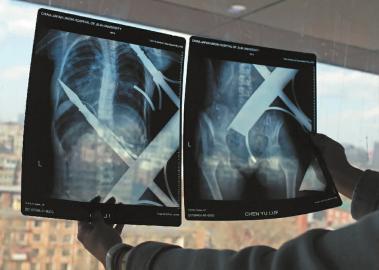

X光片顯示一根鋼筋將小女孩的右側(cè)肩膀刺穿,另外一根則從后背腰部以上靠近脊椎的地方穿入 新文化記者 白石 攝 成功把鋼筋破拆后,小雨立即被送往了手術(shù)室,接到指令后的20多分鐘里,消防戰(zhàn)士們一直在跟死亡競速。

X光片顯示一根鋼筋將小女孩的右側(cè)肩膀刺穿,另外一根則從后背腰部以上靠近脊椎的地方穿入 白石 攝

在急診室的病床上,李紅旭看到了小雨?!八龗熘跗?,意識比較清醒?!边M(jìn)一步觀察,李紅旭一時(shí)說不出話來———一根鋼筋穿透小雨右側(cè)肩膀,另一根則從后背腰部以上靠近脊椎的地方穿入,從小雨左肩部分穿了出來。兩根鋼筋由兩根角鐵連接,距離事發(fā),小雨背著這片鐵柵欄已經(jīng)近7個(gè)小時(shí)了。